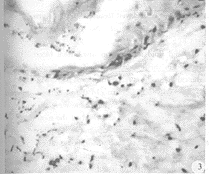

1. MEBT组:伤后第1天,表皮细胞凝固性坏死,真皮浅层胶原纤维变性、肿胀、疏松;毛囊上皮变性,毛细血管内皮细胞核固缩,其管腔内血液凝集或淤滞,仅见血管周围有少量中性白细胞浸润(图1)。伤后第3天,表皮细胞与其坏死之附件上皮空泡化,真皮浅层胶原纤维呈玻璃样变,其深层血管轻度扩张充血,可见散在的炎性细胞(以中性白细胞为主)浸润。伤后第5天,创面组织表层液化性坏死、剥脱,其内有较多中性白细胞浸润,间有少量淋巴细胞和单核/巨噬细胞(图2)。伤后第7天,前述病变明显而加重。伤后第10天,创面坏死组织液化殆尽。此时在MEBO与创面交接处以中性白细胞浸润为主,混杂少数巨噬细胞,而其深部则以淋巴细胞居多,尤以毛囊、汗腺等附属器附近最为显著。可见残存的皮肤附件上皮细胞纵向增殖、平皮,继而呈舌状向创面爬行、覆盖(图3),其周围的成纤维细胞和内皮细胞亦显示增生活跃。伤后第15天,真皮层再生,其内新生的毛细血管丰富,大部分毛囊或腺体再生近完全,部分创面已由鳞状上皮覆盖,仍有一些炎性细胞浸润。愈合后新生皮肤的结构近于正常(图4)。

图3 示增生的附件上皮呈舌状向创面爬行、覆盖。伤后第10天,HE×100